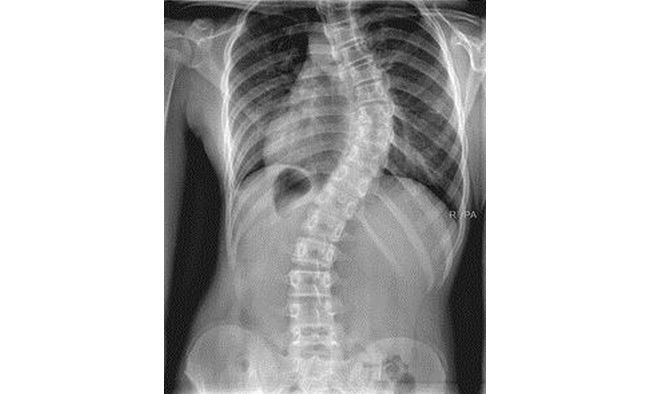

- Рентгенография. Это самое дешевое и достоверное исследование для подтверждения диагноза. С помощью этой методики специалист сможет выявить наличие патологического процесса, стадию, угол искривления с его локализацией. Кроме того, с помощью данного метода можно обнаружить наличие и других патологических процессов костной системы, таких как остеохондроз.